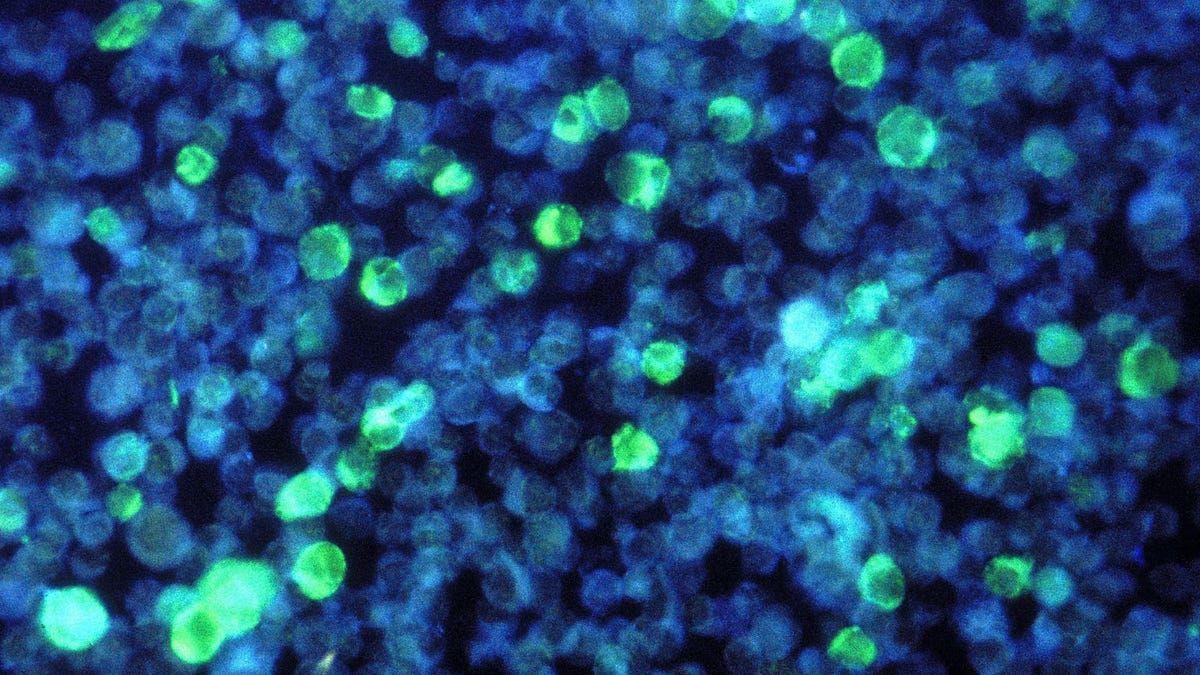

El virus Epstein-Barr es uno de los más comunes, y en algún momento de nuestra vida lo padece hasta el 90% de la población de todo el mundo. Pero un estudio de la Universidad de Harvard ha señalado a este virus, el cual provoca la conocida como enfermedad del beso, como la causa principal de esclerosis múltiple, una patología grave e incapacitante que afecta a más de 3 millones de personas en todo el mundo.

En este estudio, se llega a la conclusión de que la infección por el virus Epstein-Barr es "una causa y no una consecuencia de la esclerosis múltiple", por lo que ahora se puede decir sin miedo que este patógeno es "el desencadenante inicial" con el que deben concurrir otros factores aún desconocidos.

Los autores de la investigación señalan que uno de los tratamientos más eficaces para la esclerosis múltiple son los anticuerpos monoclonales anti-CD20. Además, consideran que hay que apuntar hacia este virus para poder tener fármacos más eficaces en el futuro.